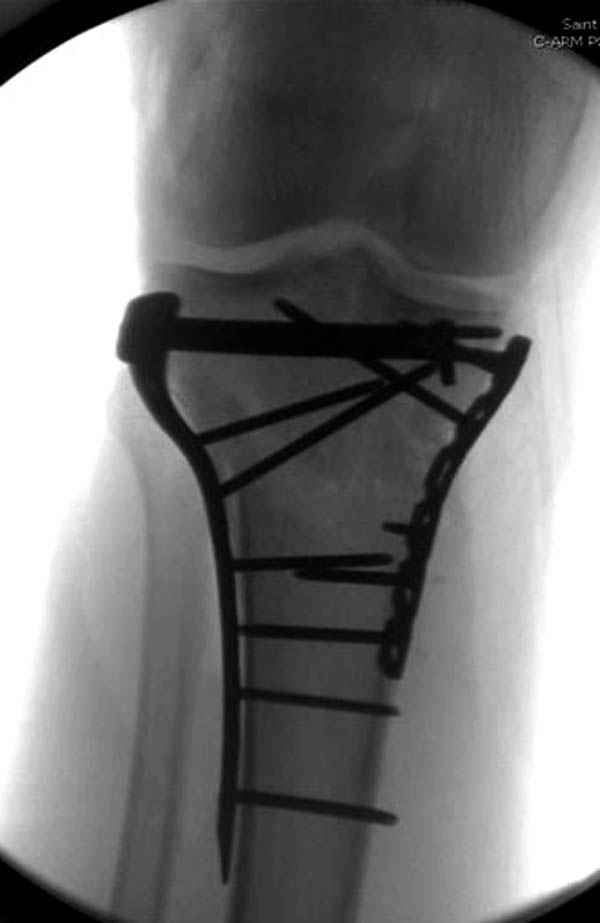

При сложных переломах тибиал плато для своего рода Damage Control мы иногда применяем поэтапную тактику. Сперва оперируется одна сторона, а потом после рекондиции мягких тканей окончательный этап.

Если состояние мягких тканей позволяет, я бы предложил такой метод для вашего больного. Без предварительного планирования будет трудно, но шанс не надо упускать. Всего несколько дней после операции, и такая тактика лучше, чем недовольный молодой пациент.

Доступ к медиальной стороне задний или медиальный, через pes или в пространстве между medial gastroc мышцы.